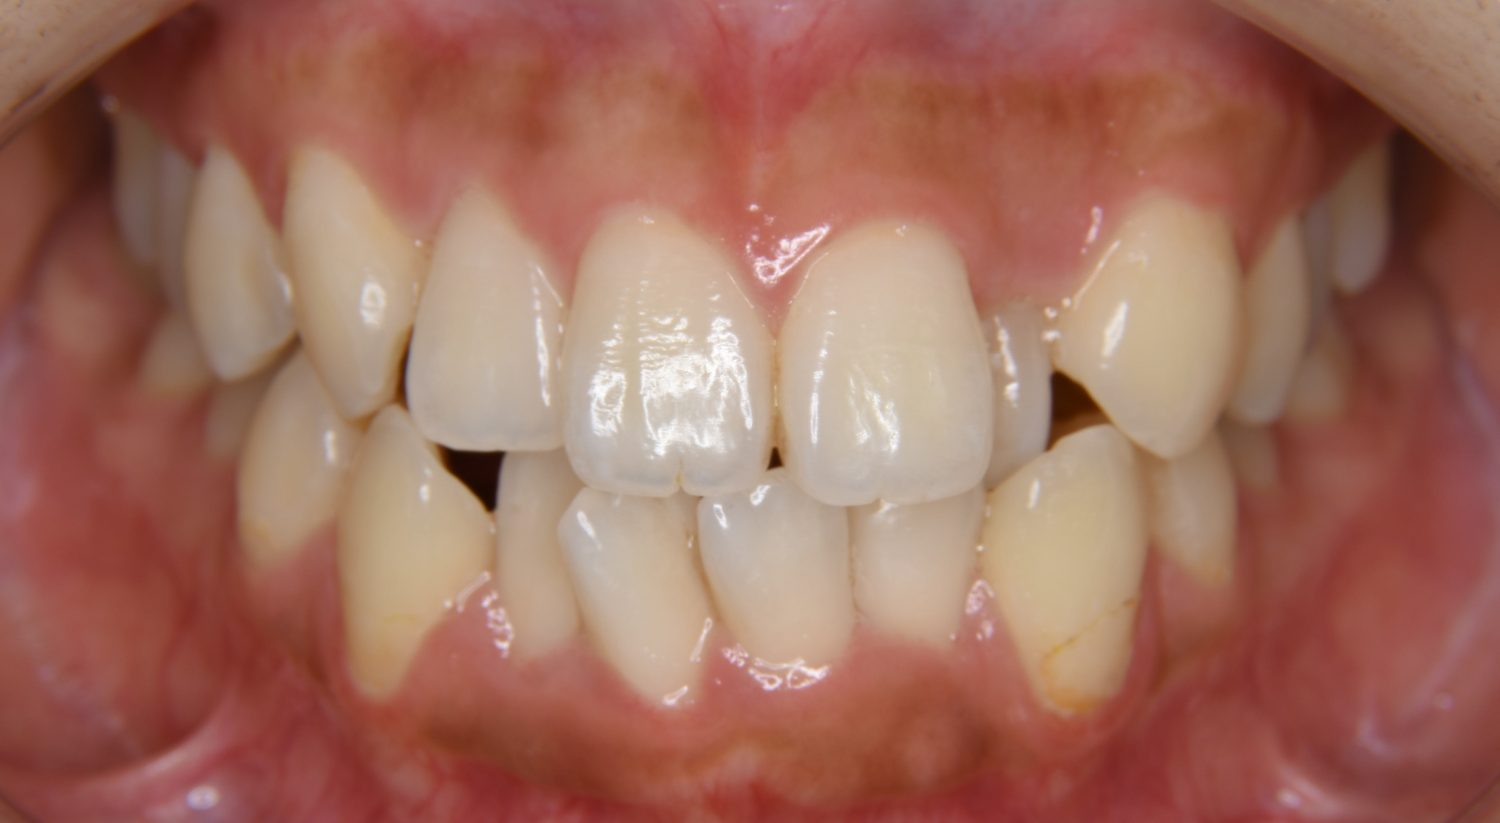

前歯部開咬の症例紹介①

Before

主訴

前歯が開いているのが気になる。

治療内容

上リンガルブラケット(舌側装置)、下ラビアルブラケット(唇側装置)に矯正用アンカースクリューを併用し非抜歯で治療を行いました。

上下の前歯が開いており前歯では全く噛めていない状態でした。臼歯の圧下を行うことで前歯でも咬合できるようになり機能面のみでなく審美面も著しく改善しました。